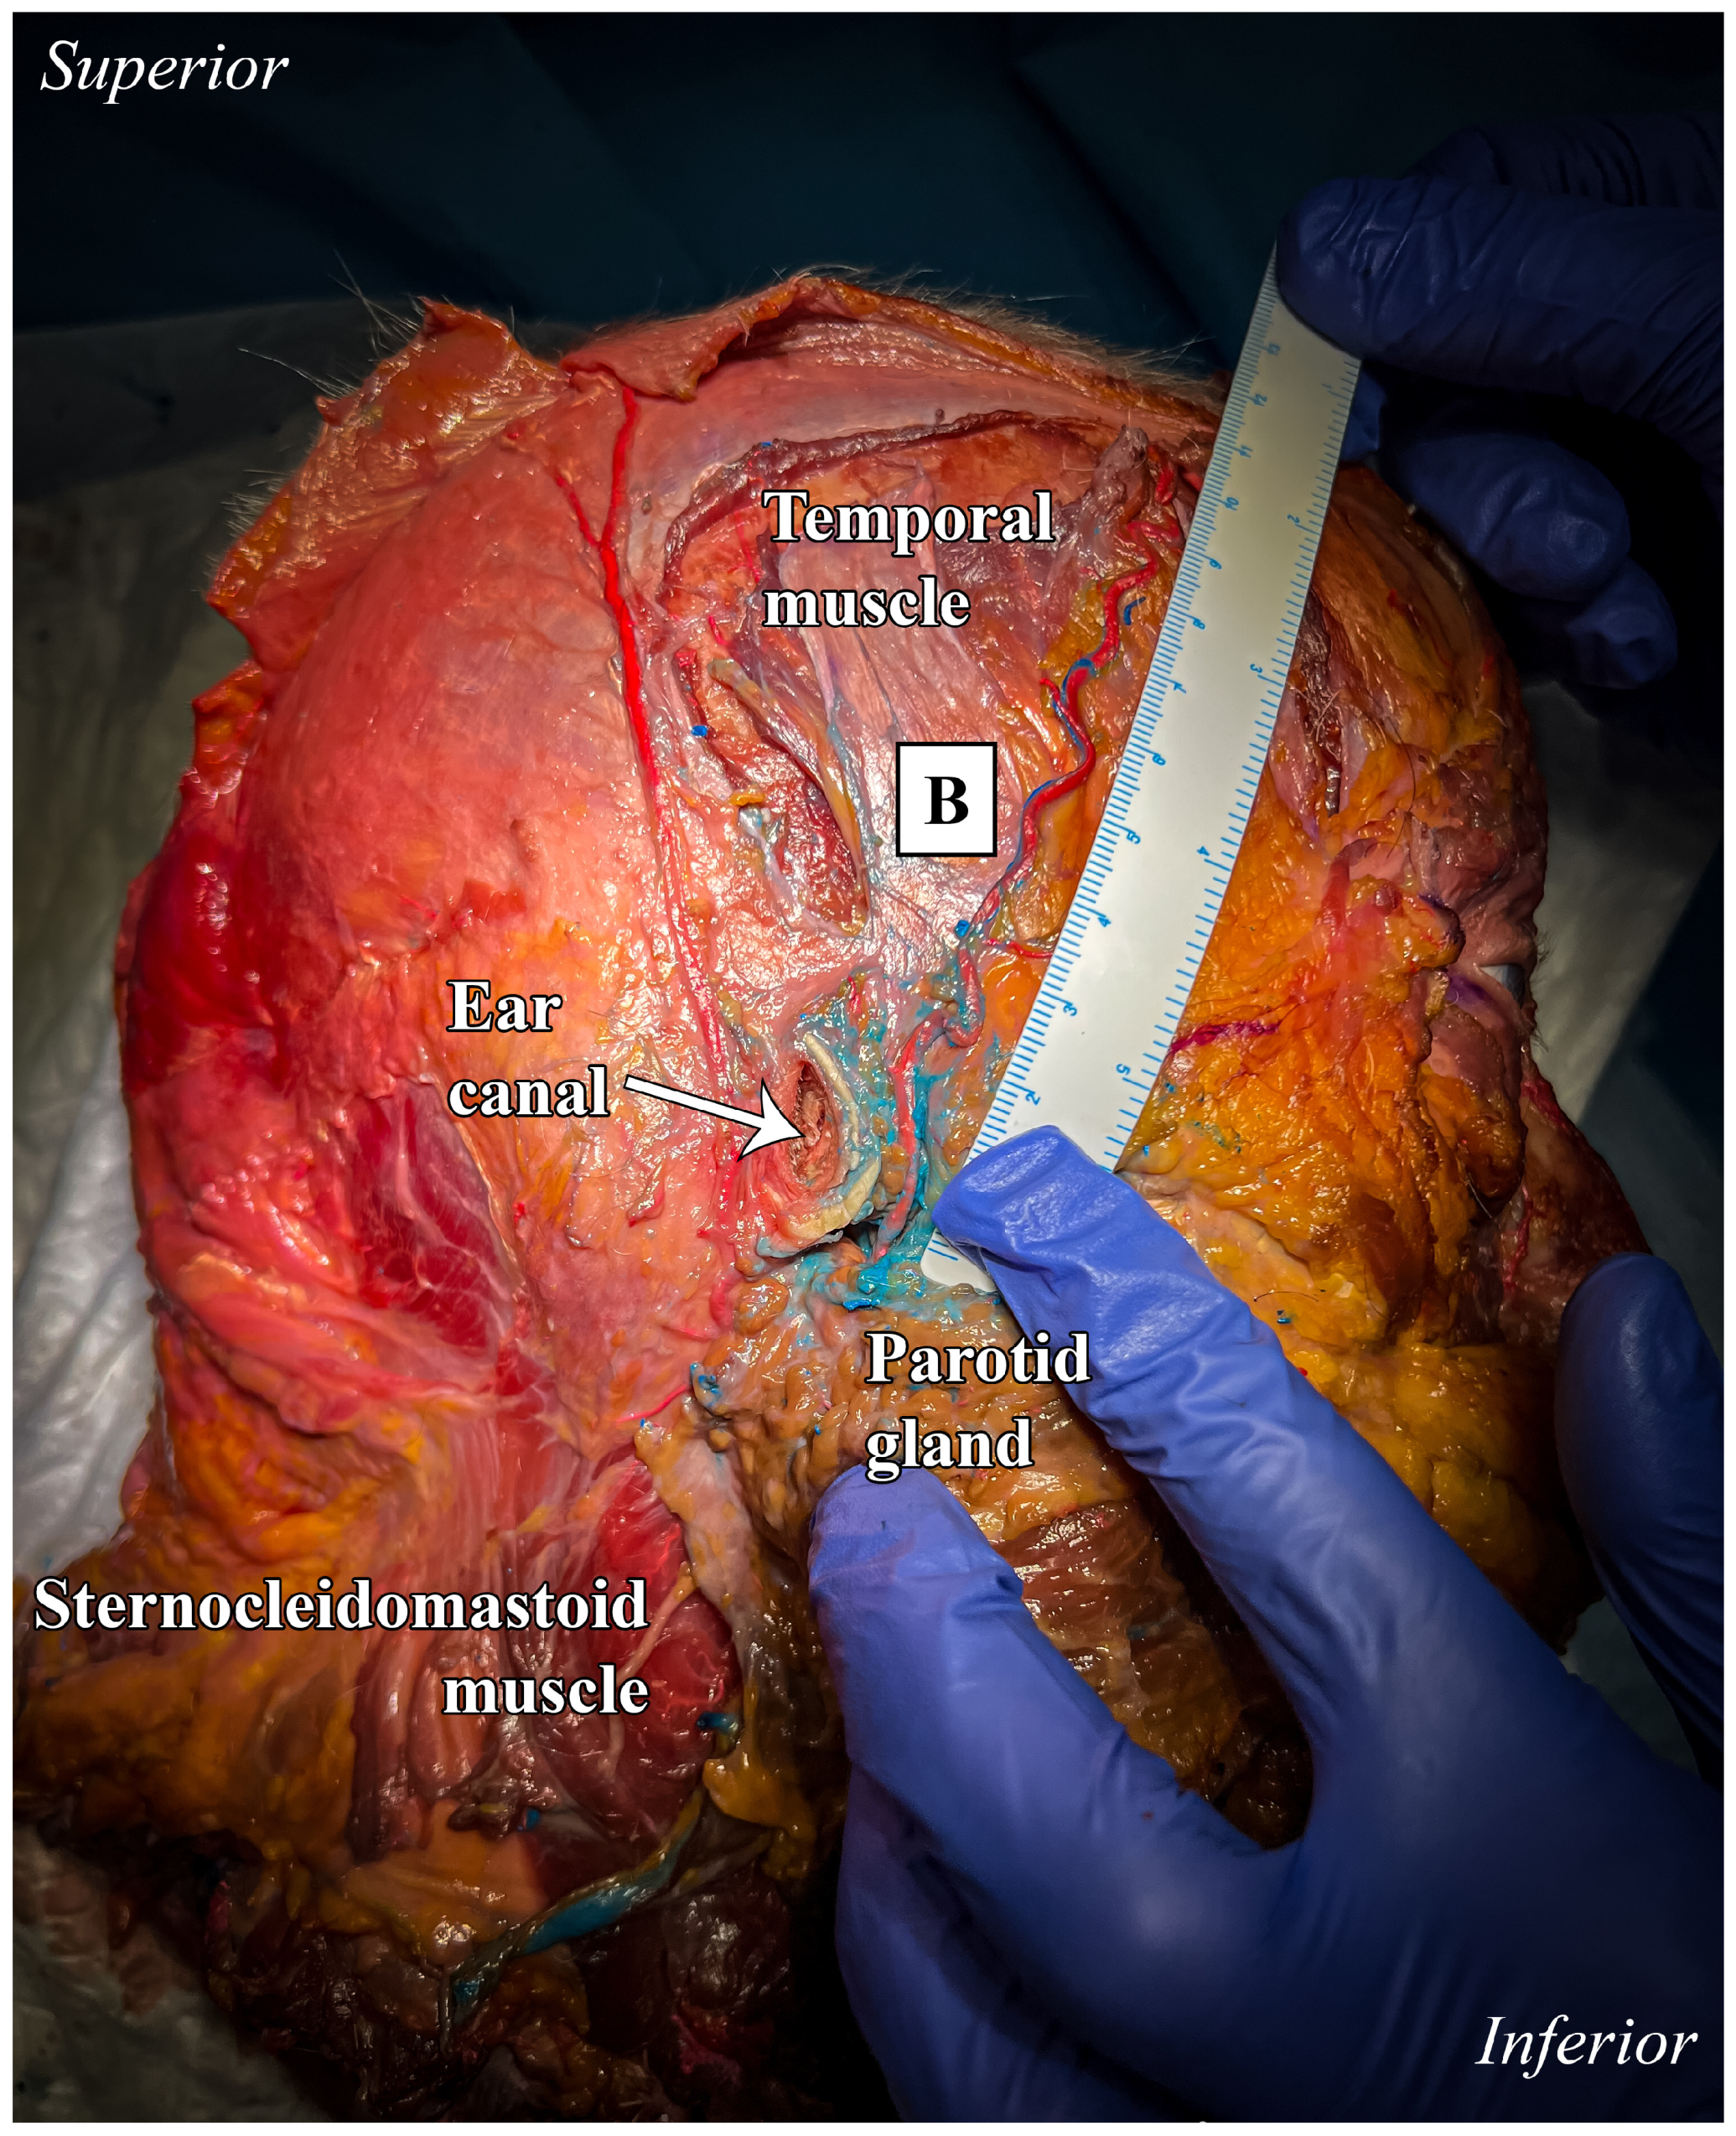

The posterior branch, corresponding to the parietal ramus, followed a course posterior to the external auditory canal; after that, it followed the galea aponeurotica above the mastoid region, extending superiorly and posteriorly. It covered a region typically supplied by the posterior auricular artery, with a measured length of approximately 13 cm (Figure 6).

Figure 6. Lateral view of anatomical preparation: temporal, infra-temporal, and parotid regions. Parietal branch (A). A ruler was used as the scale bar, providing an accurate reference for proportional measurements.